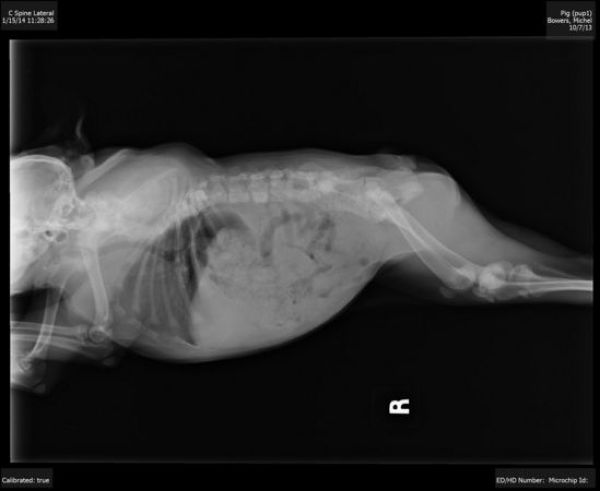

Соцмережами розлетілися фото собаки на прізвисько "Хрюша", що народилася без шиї.

Як повідомляє портал Dogpage, тваринці дуже пощастило в житті. Вона народилася від дикої собаки в лісі. Однак, мати недовго дбала про щеня. Крім того, у малечі виявилося кілька вроджених дефектів: деформація кісток і відсутність шийних хребців.